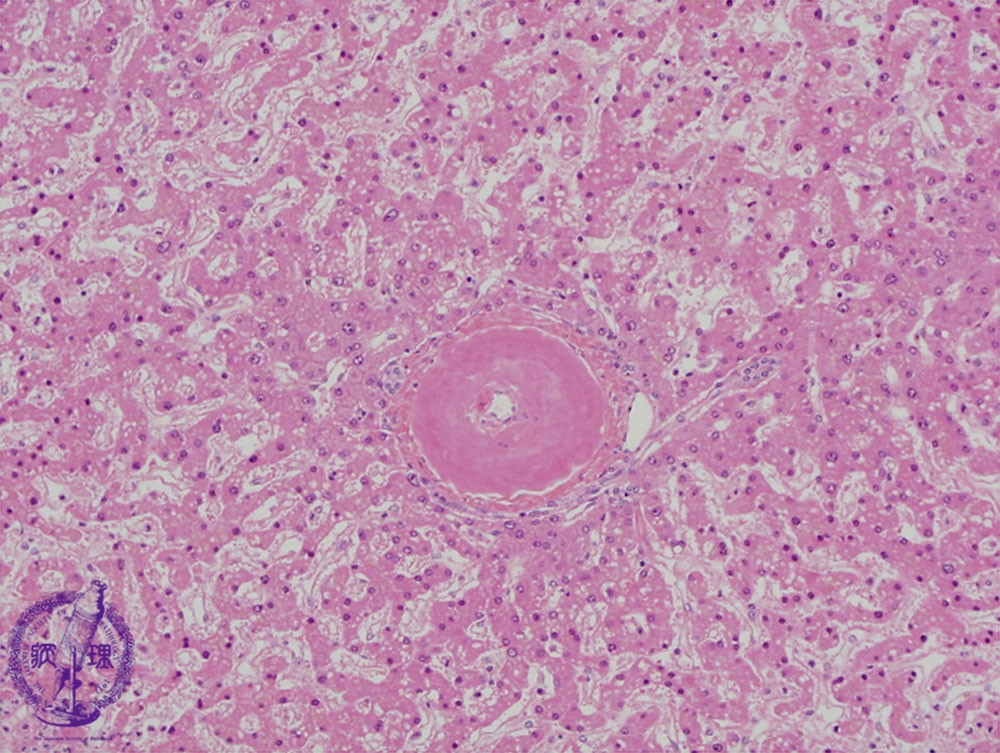

- (7)hepatic amyloidosis

Microscopic image (HE stain, high power): There is perivascular deposition of an eosinophilic amorphous material.